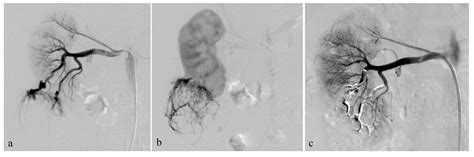

• Selective Arterial Embolization (SAE): A minimally invasive procedure where doctors inject substances into the blood vessels feeding the tumor to “starve” it and reduce its size, effectively minimizing the risk of future bleeding.